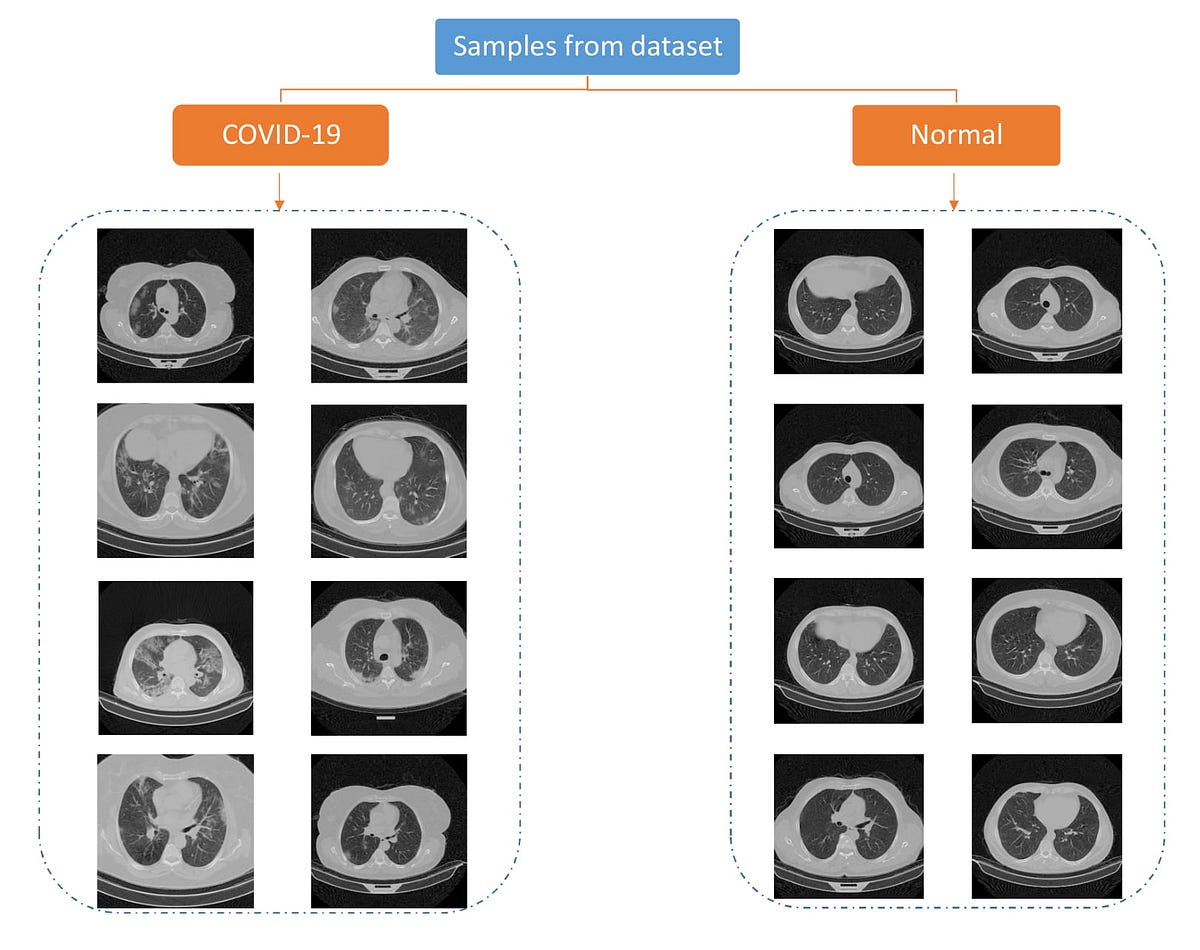

40+ Hrct Scan Chest Covid 19 PNG. Ct has a higher sensitivity but lower specificity and can play a role in the diagnosis and treatment of the disease. In an image sequence, the infection points may appear in some images and not be shown.

The diagnostic value of high resolution computerized tomography (hrct) scan chest in corona virus disease 2019. Most commonly was ggo that accounted for 120(88.9%). Ct has a higher sensitivity but lower specificity and can play a role in the diagnosis and treatment of the disease. Several full cases are reviewed, and the basic principle behind a scoring system is discussed.